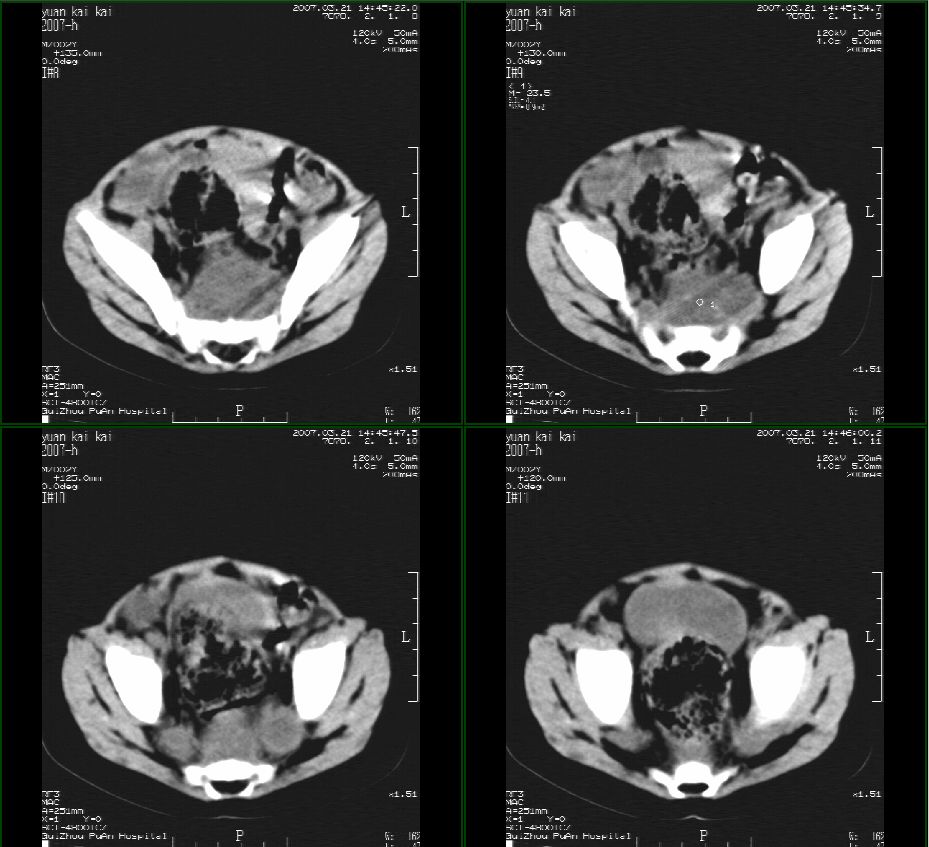

男性,2岁半,髋部疼痛10月,伴跛行,请大家会诊!

骶骨无明显吸收破坏征像,骶前见囊性占位,考虑:骶前脊膜膨出。

1骶前软组织畸胎类肿瘤。2,神经源性肿瘤。3,骶前脊髓膜膨出。

考虑1:骶前脊膜膨出,2:神经源性肿瘤  3病灶上部未传完

骶前脊膜膨出(anterior sacral meningocele):位于腰骶交界处有先天椎体缺失,膨出的硬脊膜和蛛网膜通过骶骨腹侧缺损,向骶前膨出,称骶前脊膜膨出。囊内一般无神经组织,有时神经根也会疝入到囊腔内,产生临床症状。而此患者椎体未见椎体缺损。